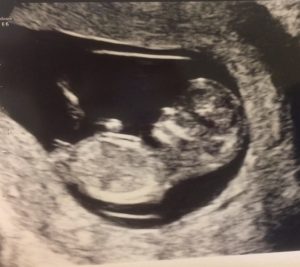

Tehotenstvo sa často opisuje ako idylický čas v živote ženy. Keď som zistila, že som tehotná, prekvapilo ma, že sa zdanlivo nič nezmenilo. Čakala som, že ma ráno prídu obliekať hrdličky, a že sa mi pod nohy budú len tak z ničoho nič sypať ružové lupene ruží. V mojich predstavách tehotné ženy ležia na obláčikoch, spoločnosť ich ovieva lopúchovými listami a od rána do večera jedia za dvoch.

Ak čakáte bábätko veľmi dobre viete, že takéto predstavy sú na míle vzdialené od reality… Celkovo tehotenstvo sa v našej spoločnosti prezentuje pekným navrch, ale keď ste na začiatku tretieho trimestra, možno vám občas napadne (ako mne), či sa to niekedy skončí a či by nemohol fungovať nejaký on/off gombík, ktorý by vám aspoň na chvíľu umožnil vrátiť sa do svojej „starej kože“.

A vôbec, ako dlho trvá kým žena otehotnie? Čo jesť, ak vám raňajšia nevoľnosť znepríjemňuje život? Hladkajú vám ľudia brucho? Aj o týchto témach hovorím v prvej epizóde môjho podcastu Jedna Mama.